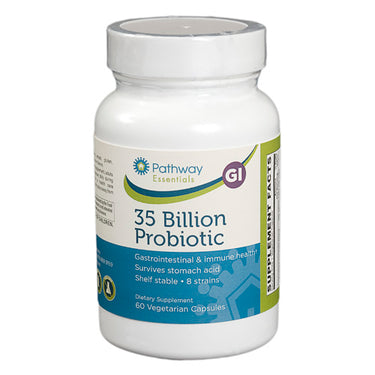

Why should I choose Pathway supplements?